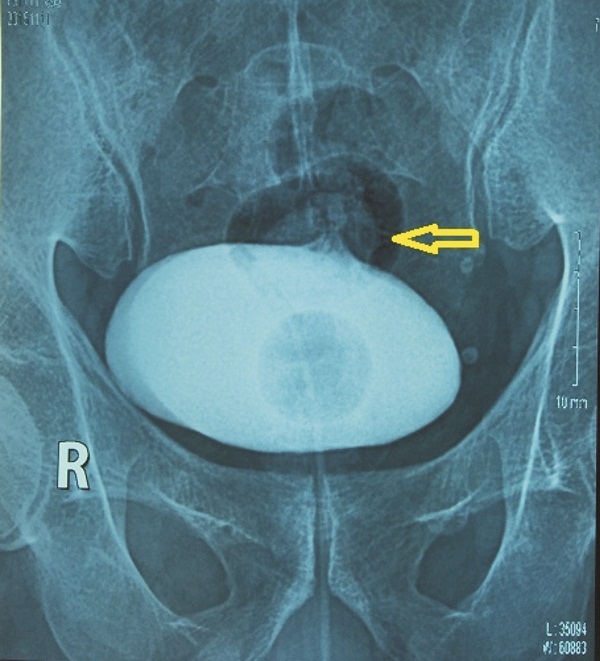

Chụp phim Cystography thấy thuốc ra ngoài bọng đái |

Chụp bàng quang bơm thuốc cản quang tan trong nước thấy thuốc đi vào đại tràng. Chụp đại tràng có thuốc cản quang không tan trong nước thấy thuốc vào bàng quang. Chụp CT bụng phát hiện có khối viêm dính từ đại tràng chậu hông vào bàng quang.